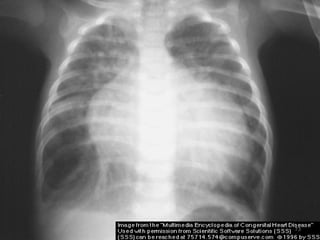

 CXR - Right. V & A enlargement

- ↑ed pulm. vascularity